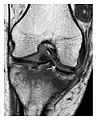

Figure 1: A 56-year-old woman presenting with left knee pain after a fall. (a) Initial anteroposterior radiograph was considered normal, however, subtle cortical disruption of the anterior rim of the medial tibial plateau, medial to the tibial spine, is noted (arrow). (b) Coronal T1-weighted MRI confirms the cortical disruption (arrow) and shows extensive fracture through the proximal tibia. (c) Coronal proton density-weighted image with fat saturation shows extensive edema in the subchondral bone. Note also hypersignal adjacent to the medial collateral ligament corresponding to a grade I sprain (arrowheads).[1]

a

b

c